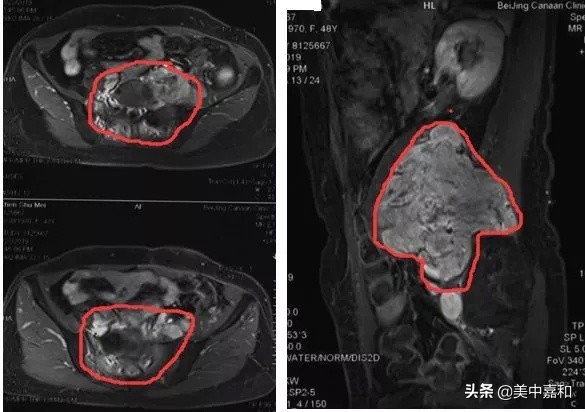

16.6*12.1cm的巨大血管瘤(画圈部分即是),侵犯骶骨和竖背肌

2019年患者左下肢再次出现胀痛并进行性加重,2019年3月28日腰骶椎MRI示:L2-S1椎体上缘水平左侧椎旁不规则肿块影,病灶累及左侧腰大肌、左侧竖脊肌并突入腰椎椎间孔进入椎管内。遂于外院就诊,外科医生发现腰骶椎及椎旁肿瘤巨大、血供丰富,手术风险较大,遂予患者安罗替尼术前靶向药物治疗。2019年5月17日腰骶椎MRI:L2-5水平左侧椎旁及左侧髂窝肿块,考虑肿瘤复发,16.6*12.1cm,肿块累及至L3/4、L4/5水平。现停止药物治疗,外科医生建议行术前放疗缩小肿瘤后争取手术机会。